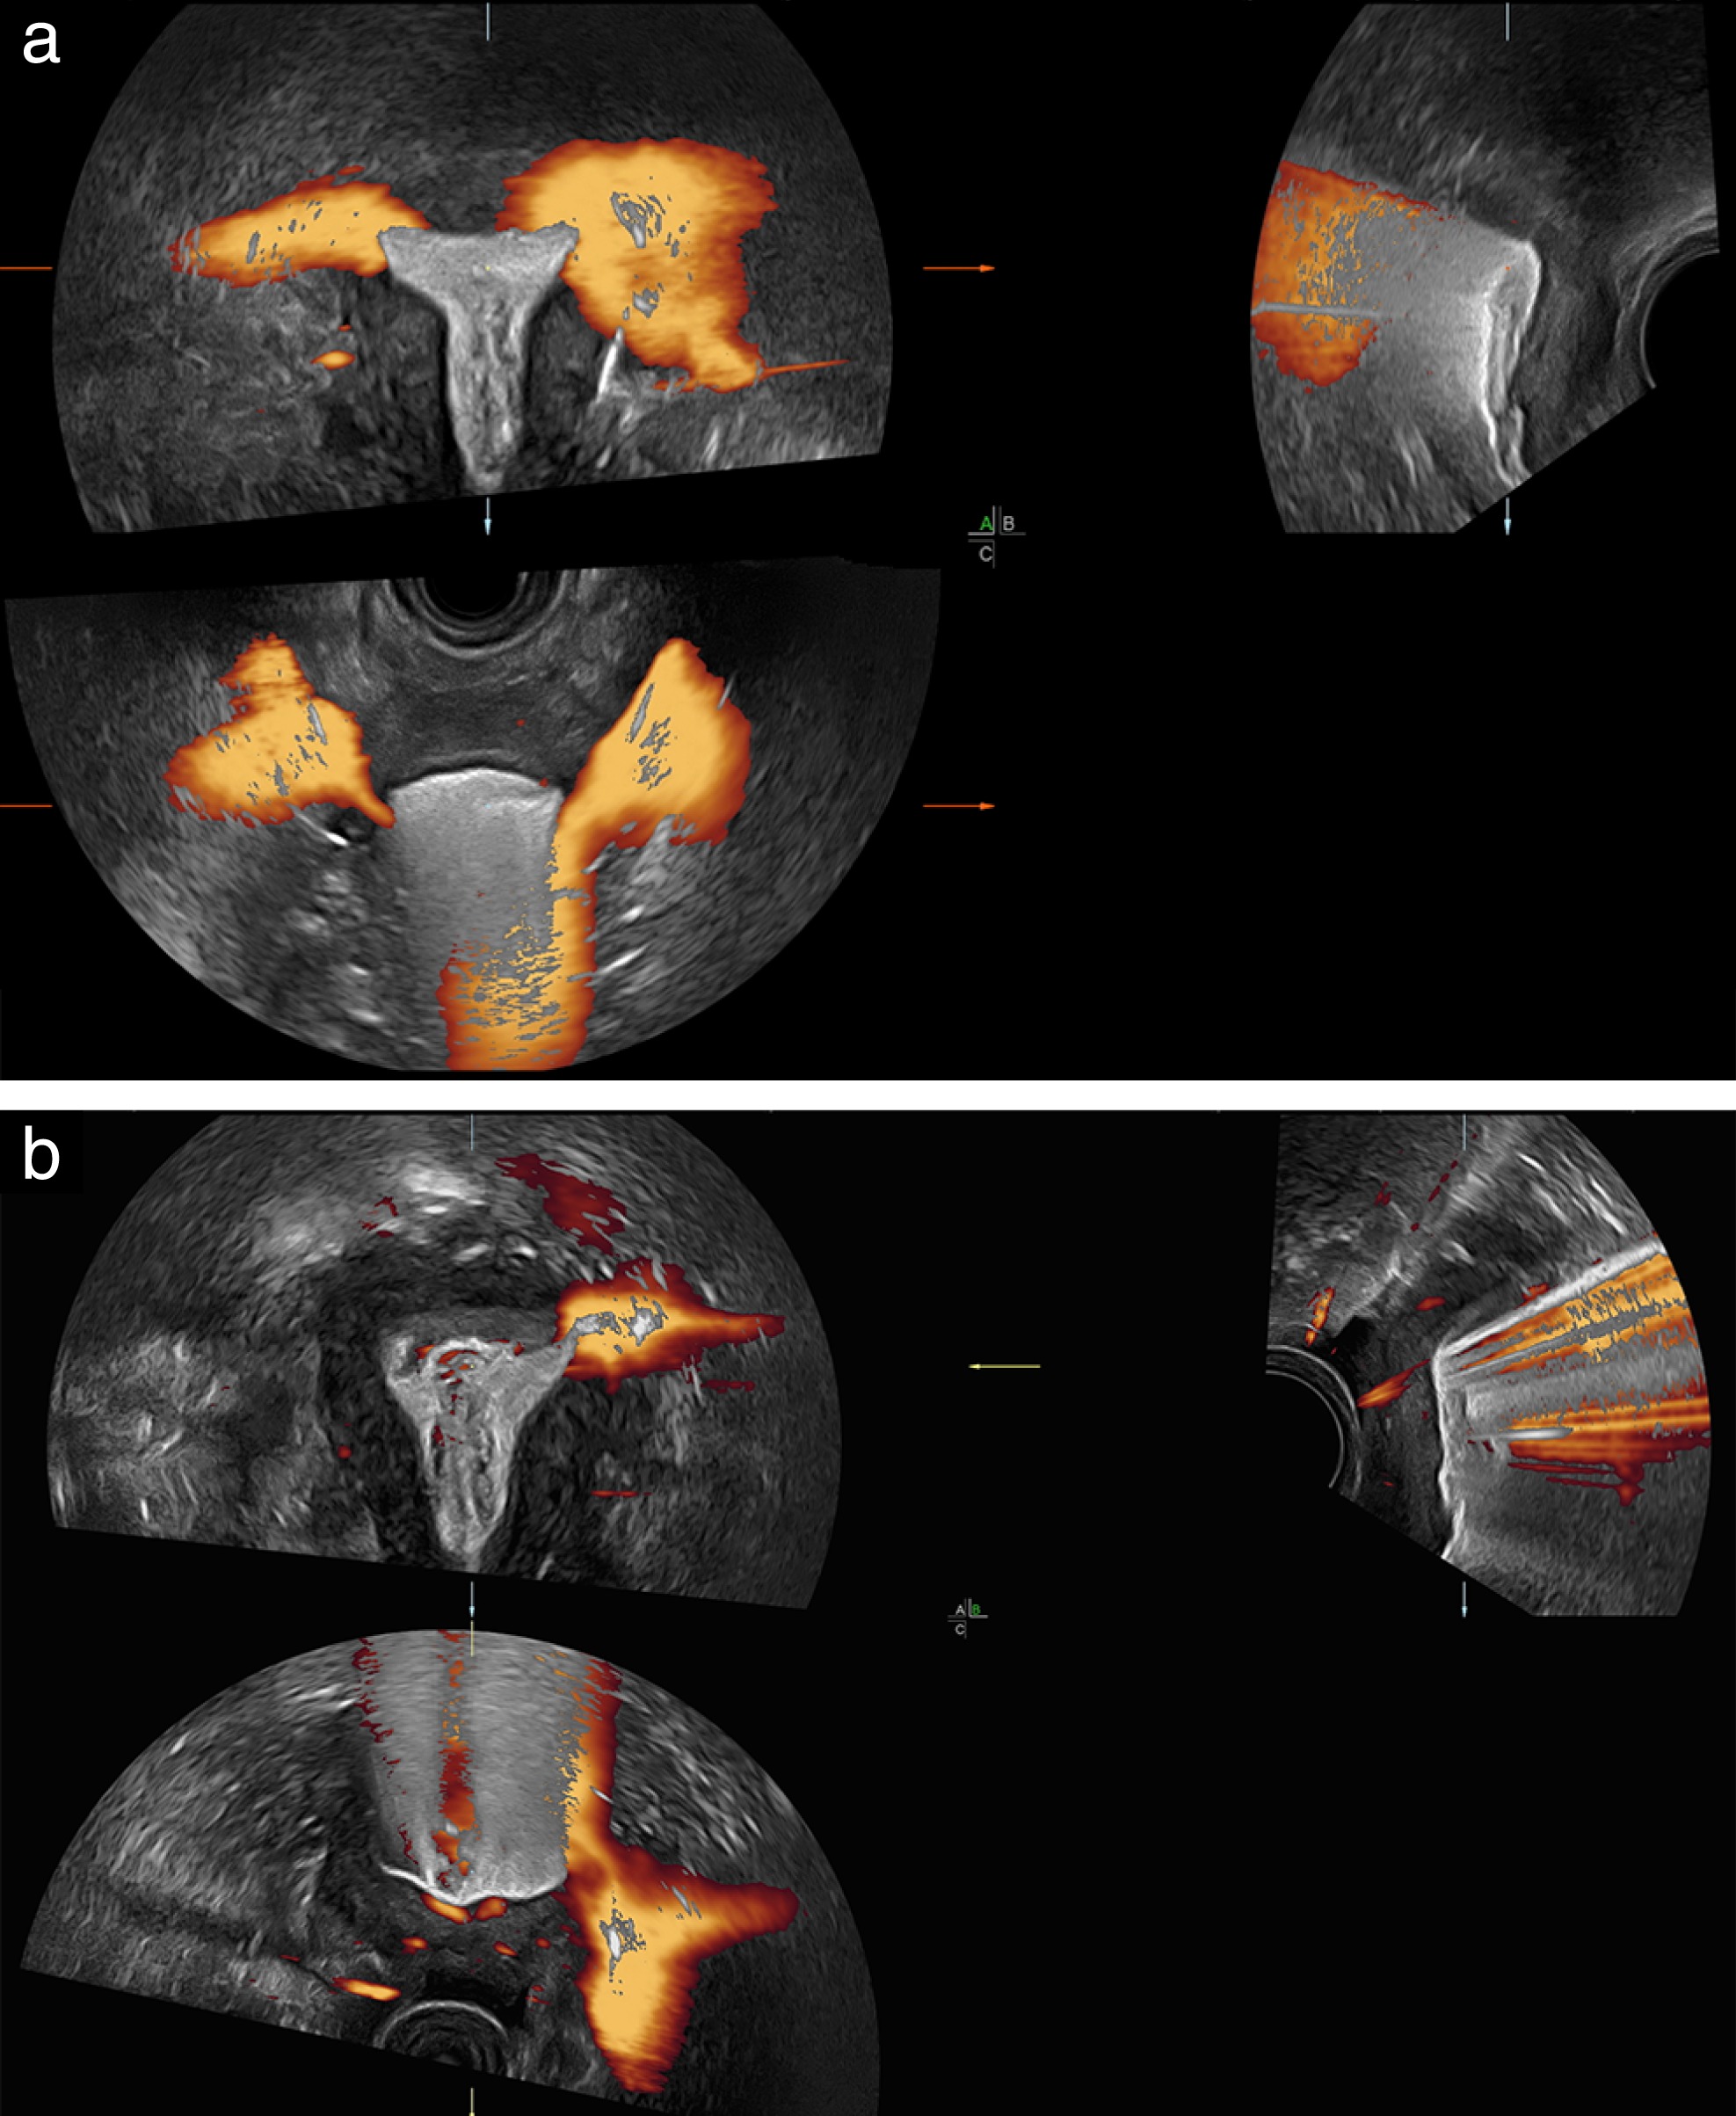

Hysterosalpingo‐lidocaine‐foam sonography combined with power Doppler imaging (HyLiFoSy‐PD) in tubal patency assessment: ‘flaming tube’ sign